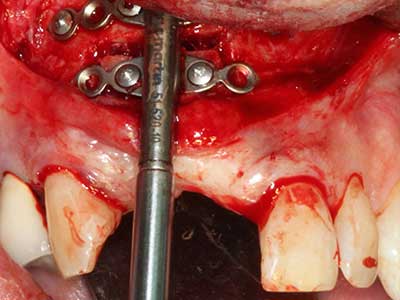

Piezo surgery has additional advantages when harvesting bone blocks. In addition to the high precision with osteotomy described above, the use of the thin saw tips specifically minimizes loss of material. Greater loss of material during harvesting can be expected with the thicker instrument tips, particularly when using Lindemann drills (Lakshmiganthan, Gokulanathan et al. 2012). The basal separation, which is necessary particularly for retromolar block transplants, is simplified by specially designed rectangular saws, with the result that piezo surgery is viewed as a precise, simple and safe procedure for harvesting retromolar bone blocks (Happe 2007) (Fig. 1-12).

Indication: Bone splitting

Bone tissue is not simply a mineral structure but also contains a substantial proportion of collagen fibres. This means it not only has good compressive strength but also a degree of flexibility, which can be taken advantage of when performing bone augmentations. In the classical expansion procedure using bone splitting, the atrophied alveolar ridge is split longitudinally and carefully expanded after reaching an adequate osteotomy depth (Fig. 13-16), ideally without substantial removal of the periosteum (Brugnami, Caiazzo et al. 2014, Stricker, Fleiner et al. 2014). Screw and plate systems with increasing expansion distance have proven effective in separating the two bone lamellae while remaining below the fracture threshold. In general, residual bone widths of at least 3–4 mm are required (Chiapasco, Zaniboni et al. 2006) to guarantee adequate flexibility and sufficient bone coverage of the future implants. If necessary, a vertical relief osteotomy on one or both sides can improve flexibility. A combination with additional augmentation techniques, particularly on the buccal side, has been described as an alternative to the classical technique.

The splitting procedure is particularly atraumatic and there is no significant loss of dimension when using piezosaws, and there are no significant differences between implants in split jaws and implants in an alveolar ridge without a bone deficit (Chiapasco, Zaniboni et al. 2006, Danza, Guidi et al. 2009). However, sufficient continuous irrigation is essential, particularly with locally restricted and deep splitting to prevent thermal stress in the apical osteotomy regions.